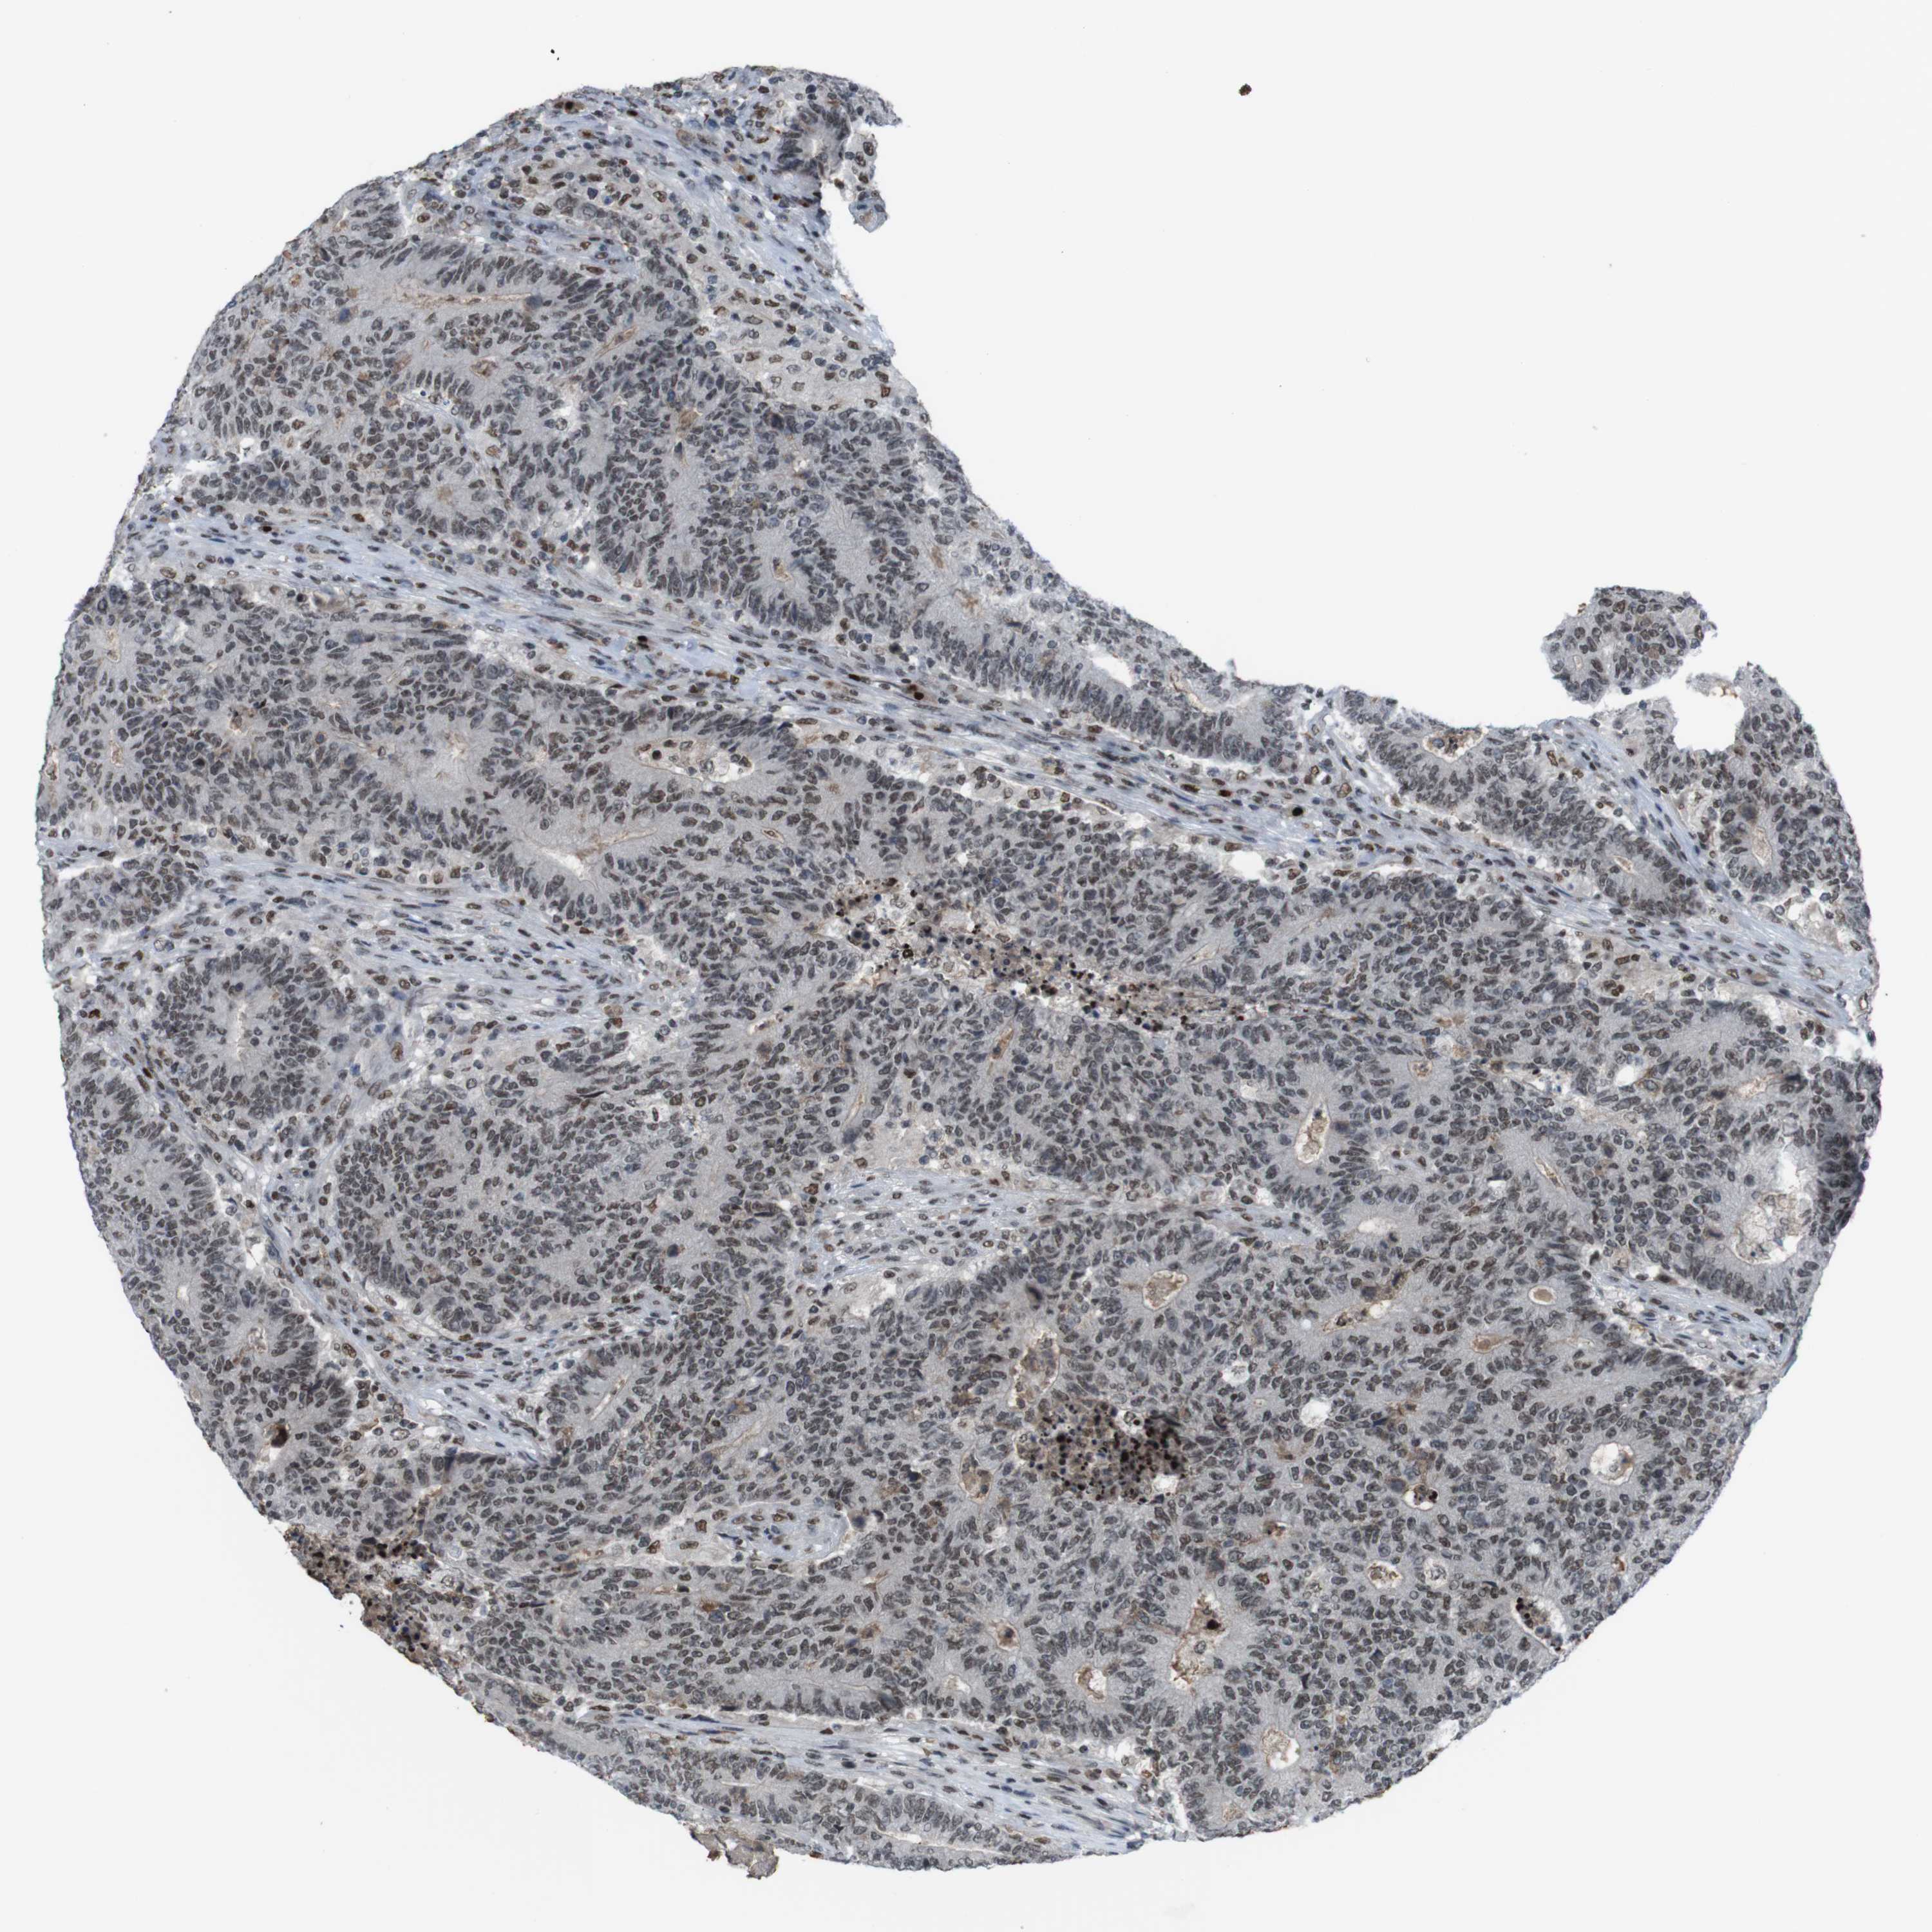

CANCER COLORECTAL CANCER Show tissue menu

Colorectal cancer

Human cancer

Colon adenocarcinoma

Rectum adenocarcinoma